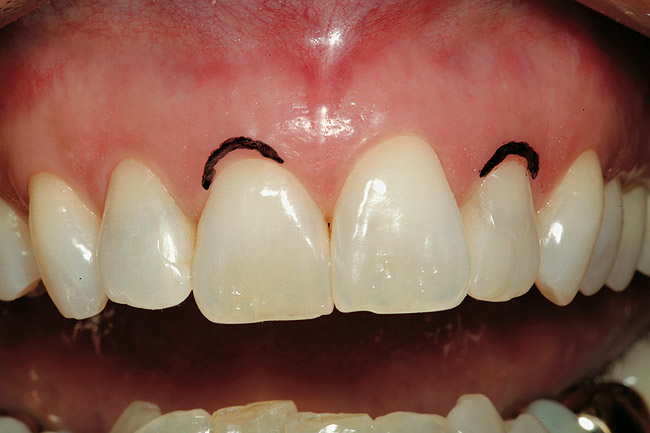

Figure 3  A gingivectomy was performed using an Er,Cr:YSGG laser to harmonize the soft-tissue levels. Biologic width was encroached upon and, therefore, a repositioning of the bony crest was also needed to prevent a relapse of the preoperative tissue position.

Figure 3